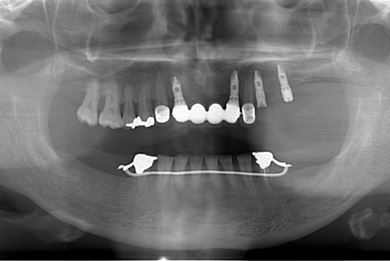

インプラントの症例写真 IMPLANT

骨再生スピードインプラント治療+セラミック治療

| 治療方針 | 上前歯部は、抜歯と同時にインプラントを埋入し、治療期間を短縮する。左上奥は、ソケットリフトにて上顎洞を拳上し、インプラント治療を可能にする。 | ||||||||||||||||||||||||||||||||

| 治療内容 | インプラント4本(ソケットリフト・抜歯即日)、テンポラリーインプラント2本、メタルボンドクラウン9本 | ||||||||||||||||||||||||||||||||